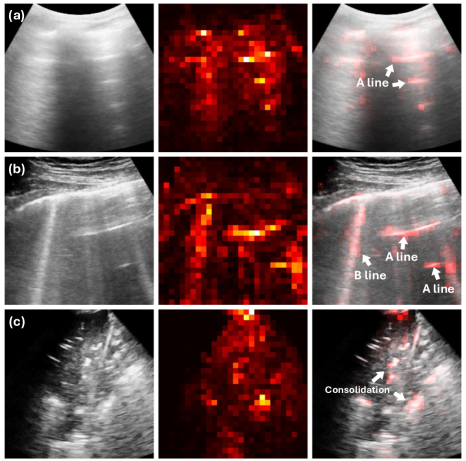

We evaluated MeDiVLAD at the frame level. For this, we trained a ResNet-50 (23.5M) as a classification baseline with a similar number of parameters to the ViT-S (21.7M) we used. The average scoring accuracy (k-NN/linear classifier) and ROC-AUC (one-vs-all) were reported. It should be noted that the k-NN accuracy is only provided for the models that were not fully supervised during training. In the upper half of Table 2, we first examined the impact of self-distillation. Without using LUS data, ResNet-50 pretrained on ImageNet (IMG) showed slightly lower classification accuracy than the other two DINO experiment sets, with the advantage of DINO becoming more pronounced after incorporating unlabeled ultrasound data. As expected, after finetuning the model with labeled frames, both accuracy and ROC-AUC improved, outperforming all other baselines (AUC: 0.9170.917 & Acc: 82.47%82.47\%). Remarkably, even without supervised finetuning, we achieved an accuracy of 75.05%75.05\%, surpassing the 71.94%71.94\% accuracy of the fully supervised ResNet-50. In Fig. 3, we present several attention map visualizations from the finetuned backbone. In (a) and (b), the attention maps accurately highlight both A-lines and B-lines, while in (c), the model identifies all regions of consolidation, offering clear insights into its decision-making process for LUS scoring.

Refer to caption

Fig. 3: Typical visualization of attention maps extracted from our pretrained ViT-S/8 (after finetuning).